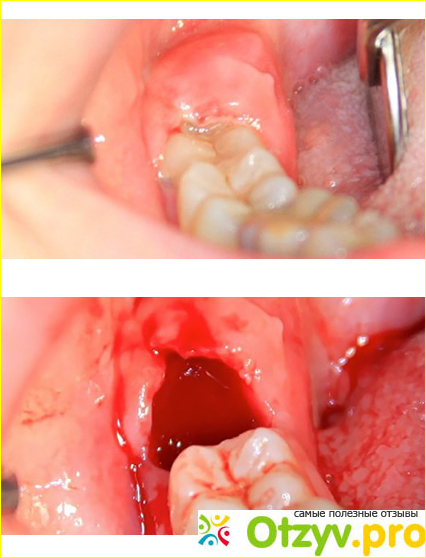

Операция заняла примерно 50 минут. Сначала пришлось разрезать десну, потом бормашиной снимать костную часть, а потом, учитывая факт, что зуб сидел «мертво» - его пришлось распиливать на части. Боли в общем не было, только через 40 мин, примерно в конце вмешательства начали появляться болевые симптомы, которые были ликвидированы повторной анестезией.

Самое противное в этой операции именно послеоперационный период – придется сидеть несколько дней на обезболивающих – типа кетанов, нимесил, поскольку рана там получается конкретная. Слабонервным лучше вообще на это не смотреть. Другу эту рану ушили саморассасывающимися кетгутовыми нитями, потому что была вероятность, что края не сойдутся.